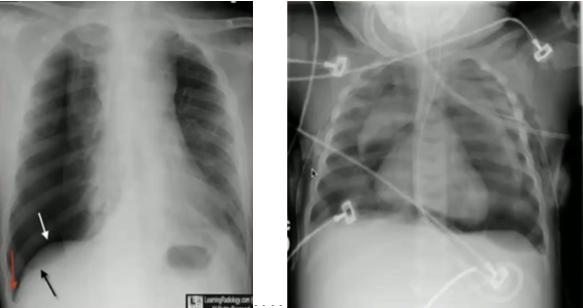

图21.气胸(左):心缘旁见气胸线;纵隔气胸(中):气胸线延伸到肺下野,可通过纵隔延伸至皮下软组织,颈部、胸前多见;心包积气(右):积气限制在心包区域

图22.仰卧位气胸(左):深沟征(大片肺野透亮,纹理消失;肋膈角较对侧深);仰卧位纵隔气胸(右):天使翅膀征(胸腺边界特别清晰,可有“漂浮感”)

图25.先天性膈疝膈疝:(左)纵隔右移,左侧肺野见充气肠管;(右)胃管位于胸腔内